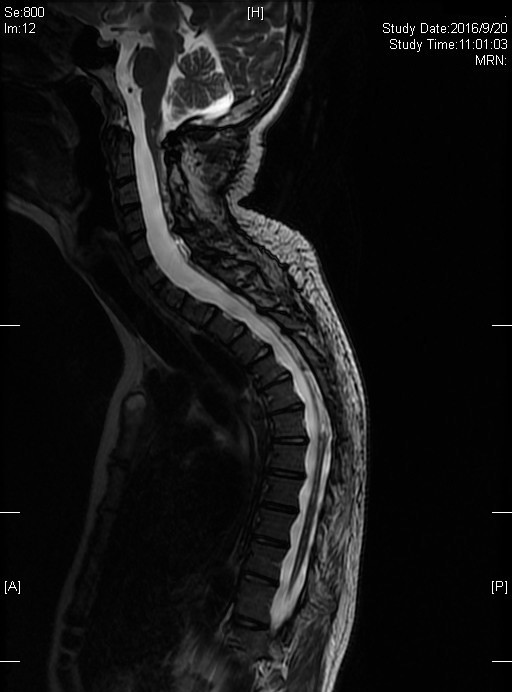

图1. 患者部分影像资料(A,术前;B,术后;C,术后1年;D,术后5年)及手术切除的肿瘤(E)

2016年09月20日,25岁的患者来到北京清华长庚医院神经外科复查。在看到患者的瞬间,11年前的手术让王贵怀教授记忆犹新,历历在目。“患者小涛是从遥远的贵州北上前来寻医,才14岁,第一次到我的诊室时是被他父亲用轮椅推进来的。” 王贵怀教授说道, “检查后确诊了小涛的病情——从脑干到第六胸椎的脊髓髓腔内生长着一条长达26厘米的肿瘤。那是我见到过的最长的肿瘤,也正因为肿瘤超长,患病两年,小涛一直没有得到手术治疗,四肢瘫痪,大小便失禁,甚至已经影响到了呼吸。

图2.术后11年的影像随访结果